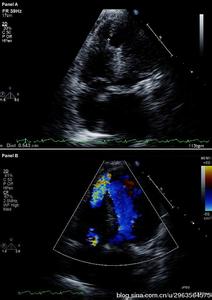

左心系统

(1)肺静脉与左心房

正位像上左心房横置于心影中部、稍偏左上、呈椭圆形,左、右肺静脉由左心房两侧呈外上、外下方向分别伸向肺野。左心房左下方经二尖瓣与左心室相连。侧位像上左心房居主动脉窗气管分叉的下方、左主支气管之前,呈纵置的椭圆形,前部与主动脉根部左窦和后窦重叠,后部与食管相邻。肺静脉在肺门处重叠于气管分叉部下方。

(2)左心室

正位像上呈斜置的长椭圆形,由内上方斜向左下方。最下方为心尖部。自心尖部向内上方至二尖瓣间为其流人道,由心尖部向内上方至主动脉瓣间为其流出道,二者重叠。左缘为左心室游离壁向左隆凸,右缘为室间隔缘向右膨隆。侧位像上,左心室略呈长方形,心尖伸向前下方,与右侧的右心室部分重叠。上端为主动脉瓣,瓣下的流出道呈圆筒状,边缘光滑。前缘为室间隔,轻度向前膨凸,下缘为左心室后壁,后缘为二尖瓣前瓣,与主动脉的左、右窦直接邻接。